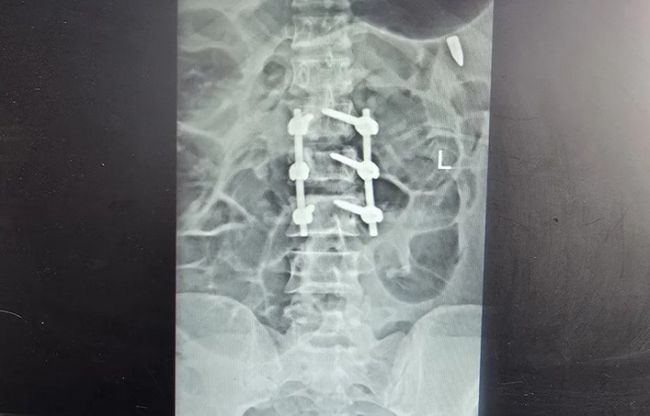

برخی از معترضان نیز با گلوله جنگی و به شکل مشخص از ناحیه اندام حیاتی هدف قرار گرفتهاند. در یکی از تصاویر رادیوگرافی گلوله یا ترکش در قفسه سینه و در ناحیه ریه مجروح دیده میشود، در تصویری دیگر گلوله جنگی در ناحیه تناسلی یک مرد قرار دارد و در موردی دیگر گلوله در نزدیکی ستون فقرات بیمار ثابت مانده است. کیانا کثیری در مورد عکس آخر میگوید: «در این عکس دو نوع آسیب را مشاهده میکنیم. یکی اصابت ناحیه پشت با گلوله جنگی، بر اساس ورود و قرار گرفتن گلوله به نظر میرسد که گلوله از بالا شلیک شده و آسیب دوم شکستگی سه مهره کمری،Lumbal Columna است که نیاز به ترمیم با فیکسیشنهای ارتوپدی داشته است.»